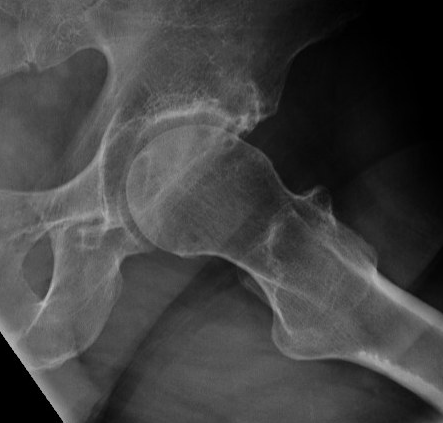

Etiology

Primary OA: 50%

Secondary OA: 50%

Secondary OA

SUFE Perthes

DDH Protrusio

Trauma

Paget's AVN

Sepsis

FAI